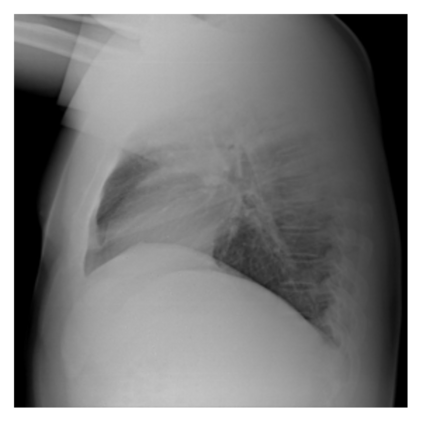

The evaluation of infectious disease processes on radiologic images is an important and challenging task in medical image analysis. Pulmonary infections can often be best imaged and evaluated through computed tomography (CT) scans, which are often not available in low-resource environments and difficult to obtain for critically ill patients. On the other hand, X-ray, a different type of imaging procedure, is inexpensive, often available at the bedside and more widely available, but offers a simpler, two dimensional image. We show that by relying on a model that learns to generate CT images from X-rays synthetically, we can improve the automatic disease classification accuracy and provide clinicians with a different look at the pulmonary disease process. Specifically, we investigate Tuberculosis (TB), a deadly bacterial infectious disease that predominantly affects the lungs, but also other organ systems. We show that relying on synthetically generated CT improves TB identification by 7.50% and distinguishes TB properties up to 12.16% better than the X-ray baseline.